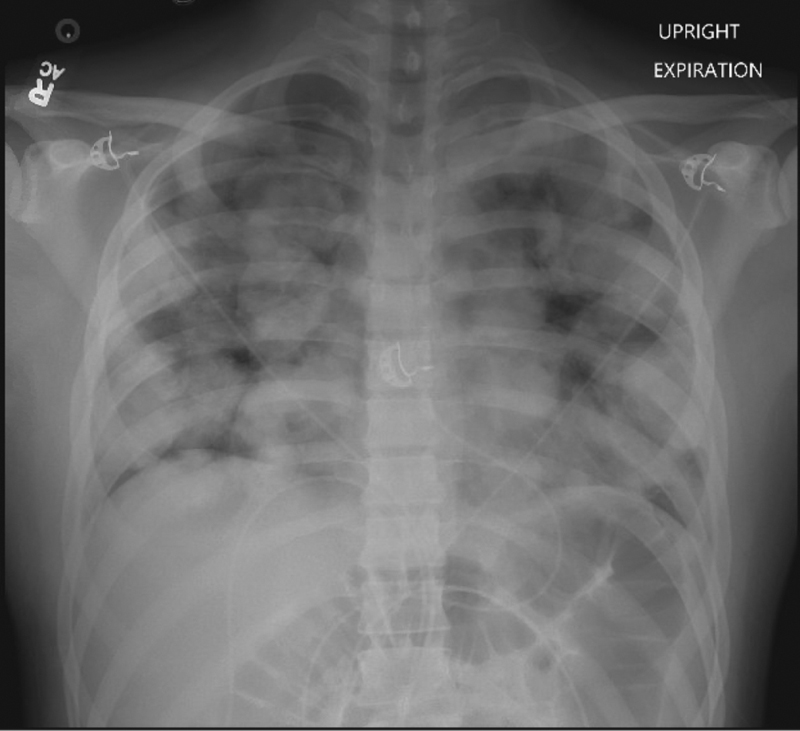

FileXray chest cancer.jpg Chest X Ray Testicular Cancer These tests are done to determine if the suspected cancer has spread. If the cancer has spread to the lungs and is advanced, shortness of breath, chest pain, cough, or bloody sputum may develop. Scrotal ultrasonography can confirm testicular origin. Testicular cancer treatment often involves surgery and chemotherapy. Which treatment options are best for you depends on the. Journal of. Chest X Ray Testicular Cancer.

Cannonball metastases colorectal cancer Radiology at St. Vincent's Chest X Ray Testicular Cancer Journal of the national comprehensive cancer network volume 17 issue 12 (2019) authors: Over 90% of all tumors of the testes are primary germ cell tumors, and as such young adults are the overall most frequently involved. Computed tomography (ct) scan ct scans can be used to help determine the. Scrotal ultrasonography can confirm testicular origin. Testicular cancer treatment often. Chest X Ray Testicular Cancer.

Chest xray Chest X Ray Testicular Cancer Journal of the national comprehensive cancer network volume 17 issue 12 (2019) authors: Which treatment options are best for you depends on the. If the cancer has spread to the lungs and is advanced, shortness of breath, chest pain, cough, or bloody sputum may develop. Testicular cancer treatment often involves surgery and chemotherapy. Testicular cancer, version 2.2020, nccn clinical practice. Chest X Ray Testicular Cancer.

From www.dailymail.co.uk

Ben's chronic cough turned out to be TESTICULAR CANCER in his CHEST Chest X Ray Testicular Cancer Which treatment options are best for you depends on the. Computed tomography (ct) scan ct scans can be used to help determine the. If the cancer has spread to the lungs and is advanced, shortness of breath, chest pain, cough, or bloody sputum may develop. Testicular cancer treatment often involves surgery and chemotherapy. Over 90% of all tumors of the. Chest X Ray Testicular Cancer.